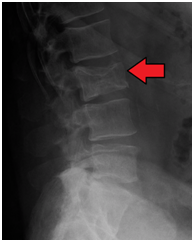

骨痛是MM最常见的症状,约70%的MM患者都有骨痛的症状,最常见的骨痛位置是脊柱和肋骨,脊柱位置的骨痛可能引发脊髓压迫和驼背。MM患者骨损伤是由于骨髓基质过度表达了RANKL的激活因子,激活RANKL蛋白,RANKL进而激活破骨细胞,对骨质进行溶解,这种骨损伤可以通过X射线识别;同时骨质的溶解导致大量钙离子流入血液,引发高钙血症。

△脊椎溶骨